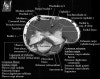

팔꿈치 관절의 MRI 단면 영상

1. Coronal section

1) Collateral ligament

2) Common extensor/flexor tendon group patholgy as well as epicondylitis